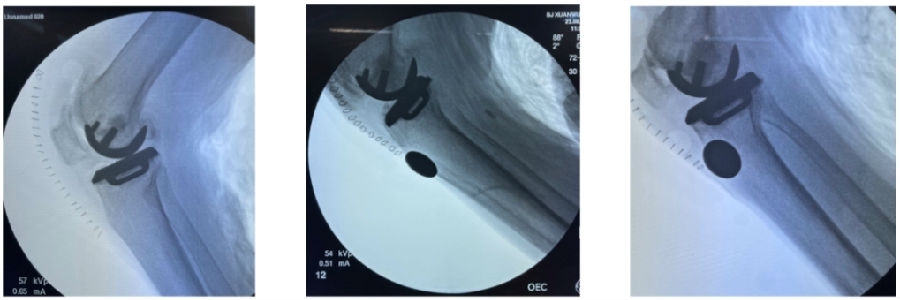

6、贴附胫骨导板

将胫骨导板置于剥离显露好的骨面,术者通过按压点向后、下、外施压,令导板与胫骨前、上和胫骨结节内侧充分贴附。按照顺序打导针,此时要注意术者按压,助手打导针,确保导针与固定孔的方向保持一致,并且导针突破二次阻力就停,不要导针过深导致后边血管神经损伤。

7、胫骨截骨

检查数据之后,进行分区截骨。垂直截骨注意避免后手抬高导致后方皮质过度切割。水平截骨在Z字拉钩保护下进行,最后截断内侧截骨槽的连接点。注意为避免锯的过程中出现震动导致的导板移位,需要在锯的过程中通过上面的按压点维持导板稳定。

8、贴附股骨导板

将股骨导板置于对应的贴附区,沿按压点向后、向外下按压,确认位置贴附满意。术者通过按压点确保导板贴附,助手按照导针顺序顺着导针孔的方向固定导针。注意在导针有二次阻力突破即停止。同时要从各个角度确认导板贴附准确。

9、股骨钻孔

分别钻4毫米和6毫米桩孔。注意助手通过按压点维持导板稳定,并顺着导孔方向钻孔。